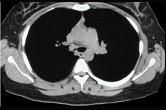

问题 47岁男性,咳嗽、胸痛、痰中带血、消瘦4个月,支气管镜、CT如图,可能的诊断是 ( )

选项 A.肺结核 B.肉芽肿 C.支气管脂肪瘤 D.错构瘤 E.气管癌

答案 E